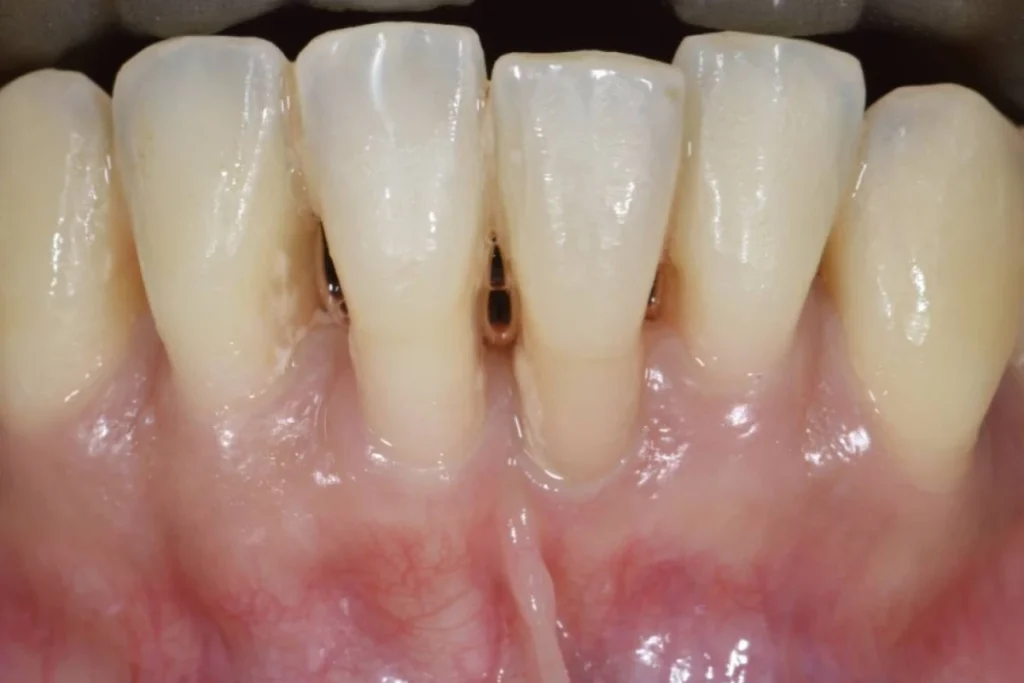

Le fait d’avoir les gencives qui se rétractent laissant apparaitre les racines des dents est appelé Récessions Gingivales.

Très souvent, ces récessions sont d’origine traumatique, dues à un brossage exercé avec une pression excessive et/ou avec une brosse à dents trop dure.

La greffe gingivale à visée esthétique est indiquée en cas de déchaussement d’une ou plusieurs racines dentaires visibles lors du sourire. Le patient consulte car il trouve ses dents plus longues et son sourire disharmonieux.

Le déchaussement peut également être à l’origine de sensibilités dentaires au chaud ou au froid car l’émail n’est pas présent sur la partie de la racine qui n’est plus recouverte de gencive. La greffe de gencive va permettre dans ces cas-là de remettre de la gencive dans la ou les zones où elle fait défaut.